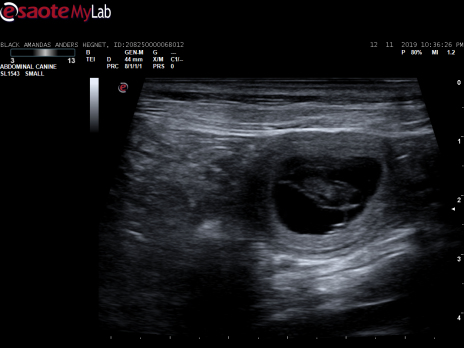

Scanningsbilleder fra den 12. november 2019

Black amandas Signed With Passioner i dag blevet scannet på Hinnerup Dyreklinik. Scanningen viste, at hun er meget drægtig.

Vi så mange fine små bobler, med hvert sit lille bankende hjerte

Herlighederne kommer til verden ca. den 20. december 2019.